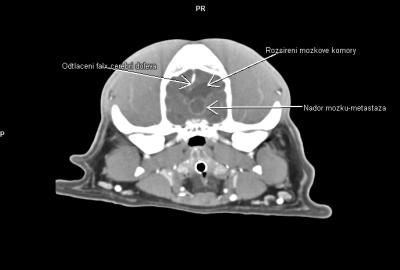

- primární a metastatické nádory mozku a mozkových plen,

V regionu hrtanu jednoznačně vedou nádory štítné žlázy(thyreoidey). Často se jedná o zhoubné varianty (karcinomy) s lokální invazivitou do struktur hrtanu a jazylky, s tendencí k tvorbě metastáz-mediastinum, plíce. Patří ale zároveň k nádorům poměrně často operovatelným. CT pak hraje v takovýchto případech zásadní diagnostickou roli.